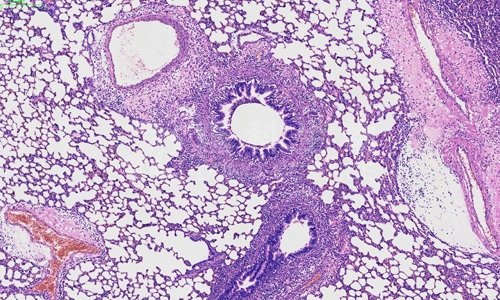

石蜡切片及染色是组织学研究中常用的技术,用于制备组织切片并进行显微镜观察。下面列举一些关于石蜡切片及染色的注意事项。石蜡切片的制备

冰冻切片和染色是病理学检测中常用的技术手段,用于研究组织和细胞的结构、功能以及病变情况。以下将介绍冰冻切片和染色在病理学检测中的意